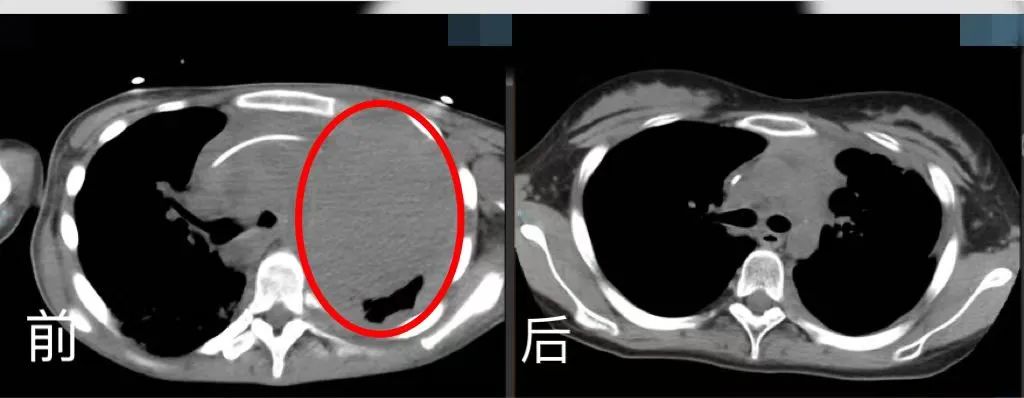

5月4日,對于17歲的少女小玉(化名)不僅是一個節日,也是她重生的日子。手捧著鮮花、笑起來甜甜的她,原本胸腔幾乎三分之二被腫瘤占滿,此刻體內腫瘤幾乎消失無形,達到臨床完全緩解狀態。

時間回溯到2022年2月,16歲的小玉因咳嗽、咳痰及咯血前往家鄉的醫院就診,隨后被診斷為原發縱膈大B淋巴瘤。由于腫瘤體積大,對縱膈的大血管及心臟產生壓迫,情況十分危急,并且腫瘤已經侵入肺部及骨髓,病情已是晚期。

在經過標準的一線治療后,腫瘤消退并不理想,隨后的靶向免疫化學二線、三線、四線治療仍無法控制病情的惡化。經過多次抗腫瘤治療,小玉的身體每況愈下、免疫功能逐漸被摧毀,加之肺部病灶大,并發嚴重的肺部感染且無法進食,體重快速下降至30公斤左右,被多位醫生判定為臨終狀態,幾乎無救治可能。

胸腔CT前后對比。四川省腫瘤醫院供圖

經過多方努力,小玉被四川省腫瘤醫院團隊從死亡線上拉回來,并為其創造了治愈的可能。

2023年1月,曙光出現——小玉胸部腫瘤達到部分緩解,從ICU轉入綜合(特需)科。